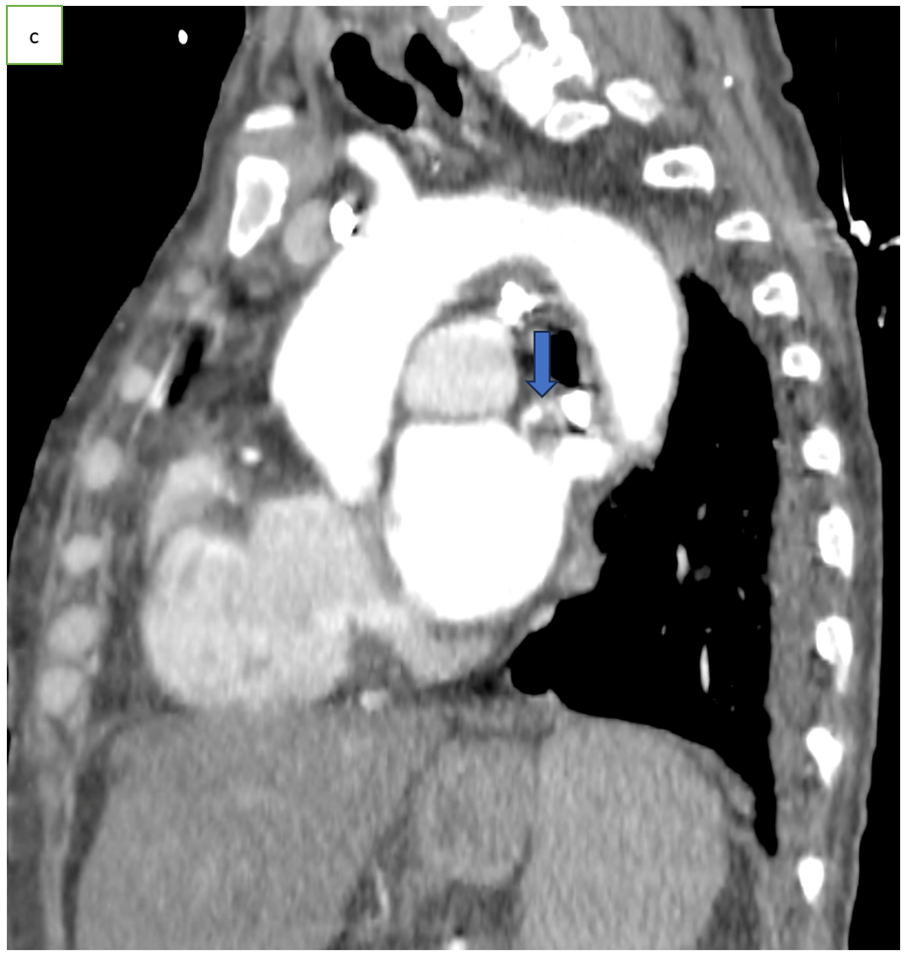

Figure 1: Axial CT scan angiography (a), coronal (b) and sagittal (c) reconstruction, showing an endoluminal thrombi in the pulmonary vein (arrow).

Chest CT angiography is the preferred imaging method, typically showing a well-defined, hypodense endoluminal thrombus in a pulmonary vein [1,3], outlined by contrast but not enhancing after injection [1].